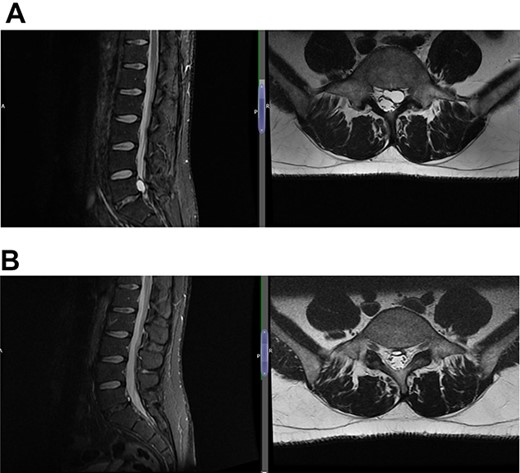

(A) Case 3—an early MRI demonstrates at L5/S1 level moderate diffuse disc bulge is seen with early bilateral facet joint degenerative changes; there is irritation of the L5 nerve roots bilaterally, and at L5/S1 level moderate left posterolateral disc bulge is seen irritating the S1 nerve roots bilaterally left more than right, and bilateral facet joint degenerative changes also noted at this level, and (B) case 3—a later MRI, the cystic changes noted at the L4-L5 level which clearly shows a connection with the intervertebral disc.

(A) Case 4—an initial MRI showing multilevel degenerative disc disease and a cyst at the lumbar L5/S1 which is causing impingement on the left S1 nerve root, and (B) case 4—comparison was made with the previous MRI; post-contrast scan shows that the L5-S1 left-sided cystic features have nearly diminished; no neoplastic lesion is detectable.